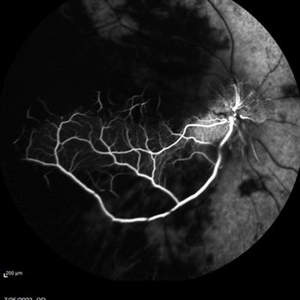

Occlusive Vasculitis Occlusive VasculitisJan 28 2023 by Anjana Mirajkar, MS Ophthalmology Central FA picture of a 40 year old female a case of occlusive retinal vasculitis. Photographer: Dr. Anjana Mirajkar -Retina Foundation, Ahmedabad. Condition/keywords: occlusive retinal vasculitis